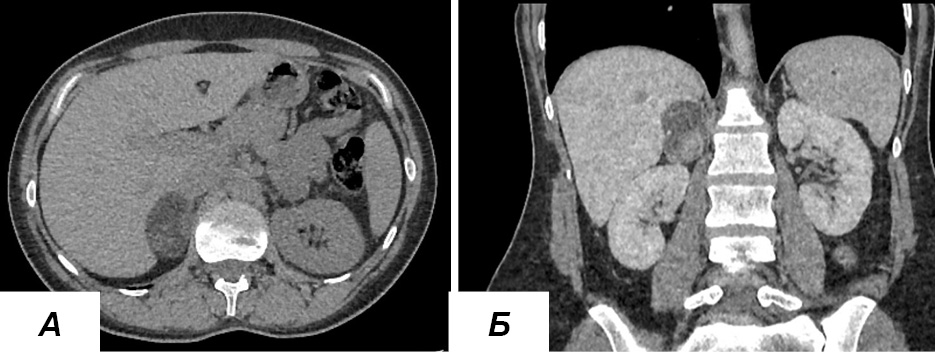

По данным мультиспиральной компьютерной томографии (МСКТ), выявленные новообразования имели доброкачественный и неопределенный фенотип и чаще всего (5 наблюдений) располагались в левом надпочечнике. Средний размер новообразований составил 40,4±8,7 мм. В одном наблюдении образование правого надпочечника имело сомнительный интраскопический фенотип, что было обусловлено большими размерами (50 мм) и неоднородностью структуры новообразования (нативная плотность -10 HU, абсолютный коэффициент вымывания на 10 мин – 52%) (рисунок 1).

Рисунок 1. МСКТ брюшной полости и забрюшинного пространства у больной с новообразованием правого надпочечника с сочетанной продукцией альдостерона и кортизола (нативная фаза): а – аксиальная плоскость, б – корональная плоскость.

Figure 1. Abdominal and retroperitoneal CT scan (a – axial view, b – coronal view, native phase) in a patient with a tumor of the right adrenal gland with combined production of aldosterone and cortisol.